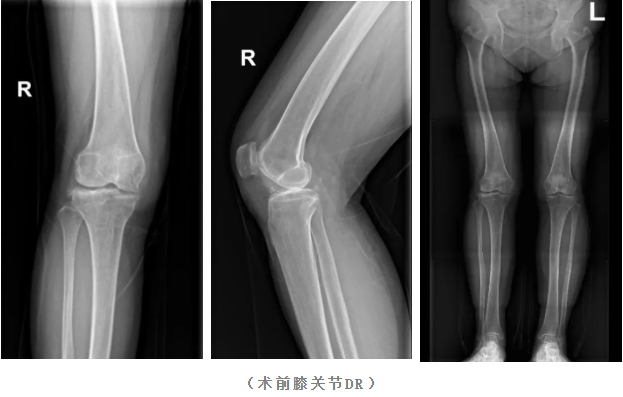

接受本次手术的患者孔大妈(化名),今年64岁,因右侧膝关节疼痛多年行走不便,通过多种保守治疗后全膝关节疼痛不仅未缓解反而持续加重。影像学检查显示,其膝关节关节间隙明显减小,并伴有明显的骨质增生,日常生活受到极大影响。

针对此类终末期骨关节炎,全膝关节置换术是国际公认的有效治疗方案。但传统手术高度依赖医生的经验,在力线重建、假体安放角度等关键环节存在一定的不确定性。为解决这一难题,省二院骨科团队决定引入机器人辅助系统,为患者实施精准化、个性化的手术。